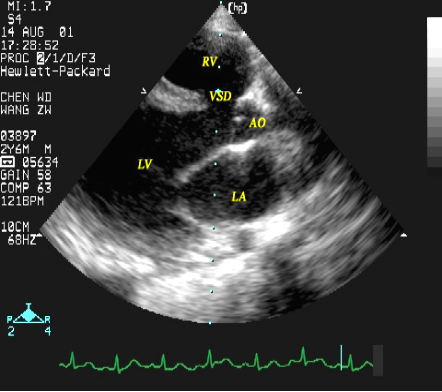

室间隔缺损:超声心动图表现

室间隔缺损(流入道部)